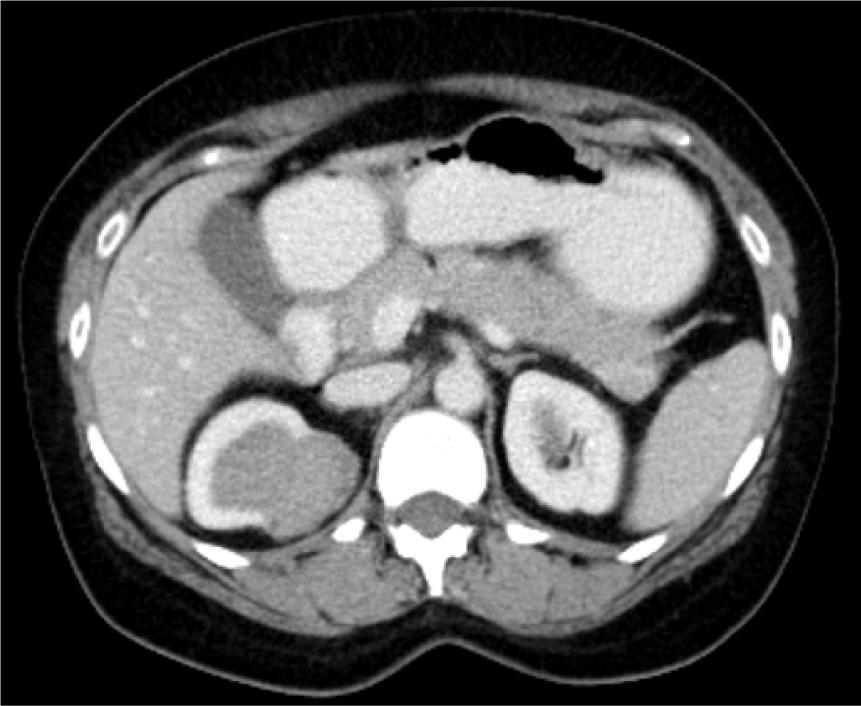

A 48-year-old female patient came with an incidentally detected right renal mass during evaluation for menorrhagia. Ultrasound evaluation for the same revealed a right renal mass. This was further evaluated with a dedicated computed tomography (CT) scan of the abdomen, which showed a solid cystic mass lesion in the right kidney’s upper pole, which was located posteromedially and measured 57*45*34 mm with obvious enhancement. There were also multiple enlarged retrocaval and aortocaval nodes, the largest measuring 25* 12 mm (Figure 1). Her serum creatinine was 0.8 mg/dL and her hemoglobin was 11 g/dL. The uterus showed evidence of multiple fibroids. She did not have any flank pain, lower urinary tract symptoms, or hematuria. She had no comorbidities or addictions. She, however, did have a family history of breast cancer. She underwent metastatic workup by an FDG positron emission tomography (PET) CT scan (Figure 2), which showed a metabolically active heterogeneously enhancing lobulated solid cystic lesion in the right kidney along with metabolically active right renal hilar and aortocaval lymph nodes. No other areas of metastasis were found.

Figure 1: Contrast-enhanced CT scan of the abdomen showing renal mass in the right kidney.

The usual CT presentation of a carcinoid tumor is a well-circumscribed, nonenhancing, or slightly enhancing mass with a solid component, but in some cases cystic components or calcifications are also seen (1, 7). According to Henry et al., in which seven cases were reviewed, 71.4% showed calcification (7). Our patient’s CT scan showed a heterogeneously enhancing lobulated solid cystic lesion with multiple regional lymph nodes.